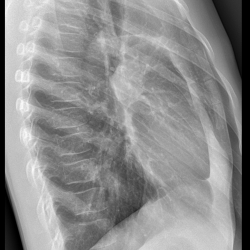

Пациентка 70 лет. Переболела КОВИДом. Жалобы на кровохарканье.